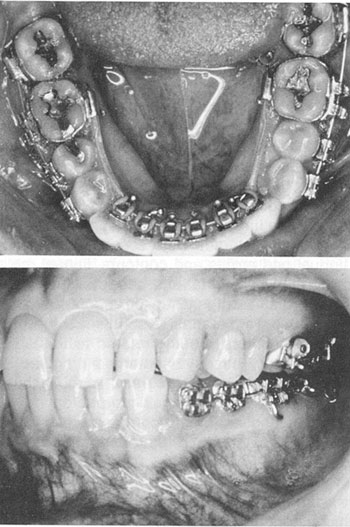

At this point in the appliance development, one of the greatest clinical problems was the difficulty in ligating the brackets. Patient acceptance appeared to be I better than expected, with tongue irritation and speech problems at a minimum. Starting in late 1979, all cases were bonded indirectly, and bracket retention was at least 90%. Initial cases were entirely lingual, including the second molars (Fig. 4). By December 1979, 40 patients were in treatment with this approach.

Fig. 4 Phase II Appliance, circa 1978-79, total lingual, second molar to second molar.